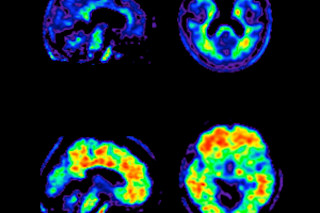

在第一种方法中,医生注射一种放射性染料,该染料会与淀粉样蛋白斑块结合,淀粉样蛋白斑块是一种积聚在患者大脑中并是该病症标志的有害蛋白质;然后,他们通过PET扫描大脑来检测染料。去年夏天,费城Avid Radiopharmaceuticals的研究人员利用该技术,在35名阿尔茨海默病患者中确诊了34名,后来通过尸检得到证实。考虑到目前被诊断患有阿尔茨海默病的患者中有20%实际上患有其他疾病——尤其是抑郁症、维生素B12缺乏症、帕金森病痴呆症或以微型中风为特征的血管性疾病——这是一个巨大的进步。